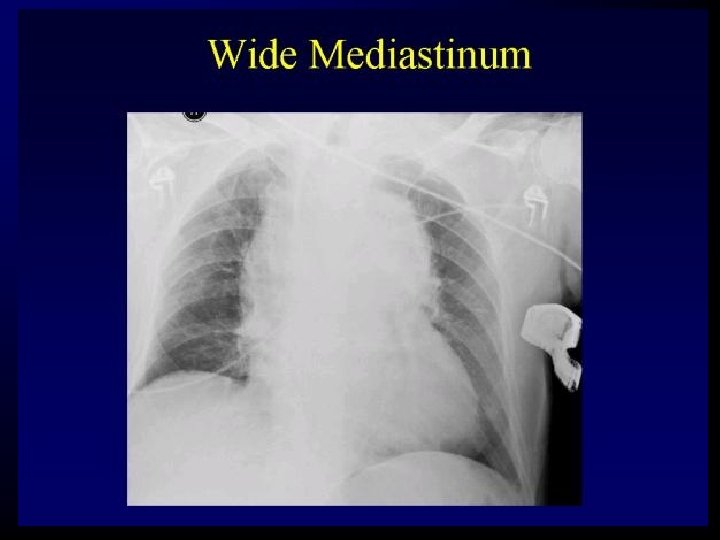

Aortic Injury : Suspicion • Mechanism – Falls> 3 m – Major decelaration/acceleration • SIGNS – Neck hematoma – Assymetic pulse or BP – Radiofemoral delay – Severe searing pain

Aortic Injury: CXR Signs • • • Mediastinum > 8 cm Abnormal Aortic contour Opaque artopulmonary window Apical cap Mediastinal displacement Fracture of first rib or scapula